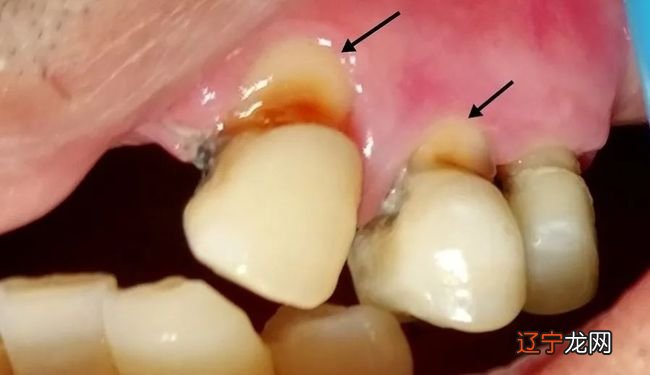

梦的一个主要来源就是生理的刺激,所以有些梦的含义就是直接反应的生理情况,比如很多人都可能做过在梦里找厕所的梦,而醒来后大多都是直往卫生间去方便,实际上这就是膀胱被尿憋涨所引起的一个梦 。因此梦见掉牙齿也可能纯粹是由于生理因素所导致的,比如虫牙或牙齿有病变等 。